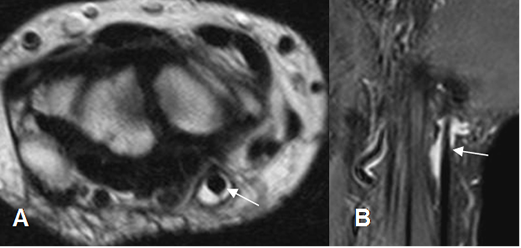

En la RM, los hallazgos son similares a la ecografía. Engrosamiento del tendón y alteración de su SI por tendinitis y presencia de liquido a su alrededor, por tenosinovitis. (Fig 90 a 93).

Fig 93. Tenosinovitis.

A: RM axial en T2 y B: RM coronal en STIR. Tendón del extensor ulnar del carpo rodeado por líquido, secundario a tenosinovitis.